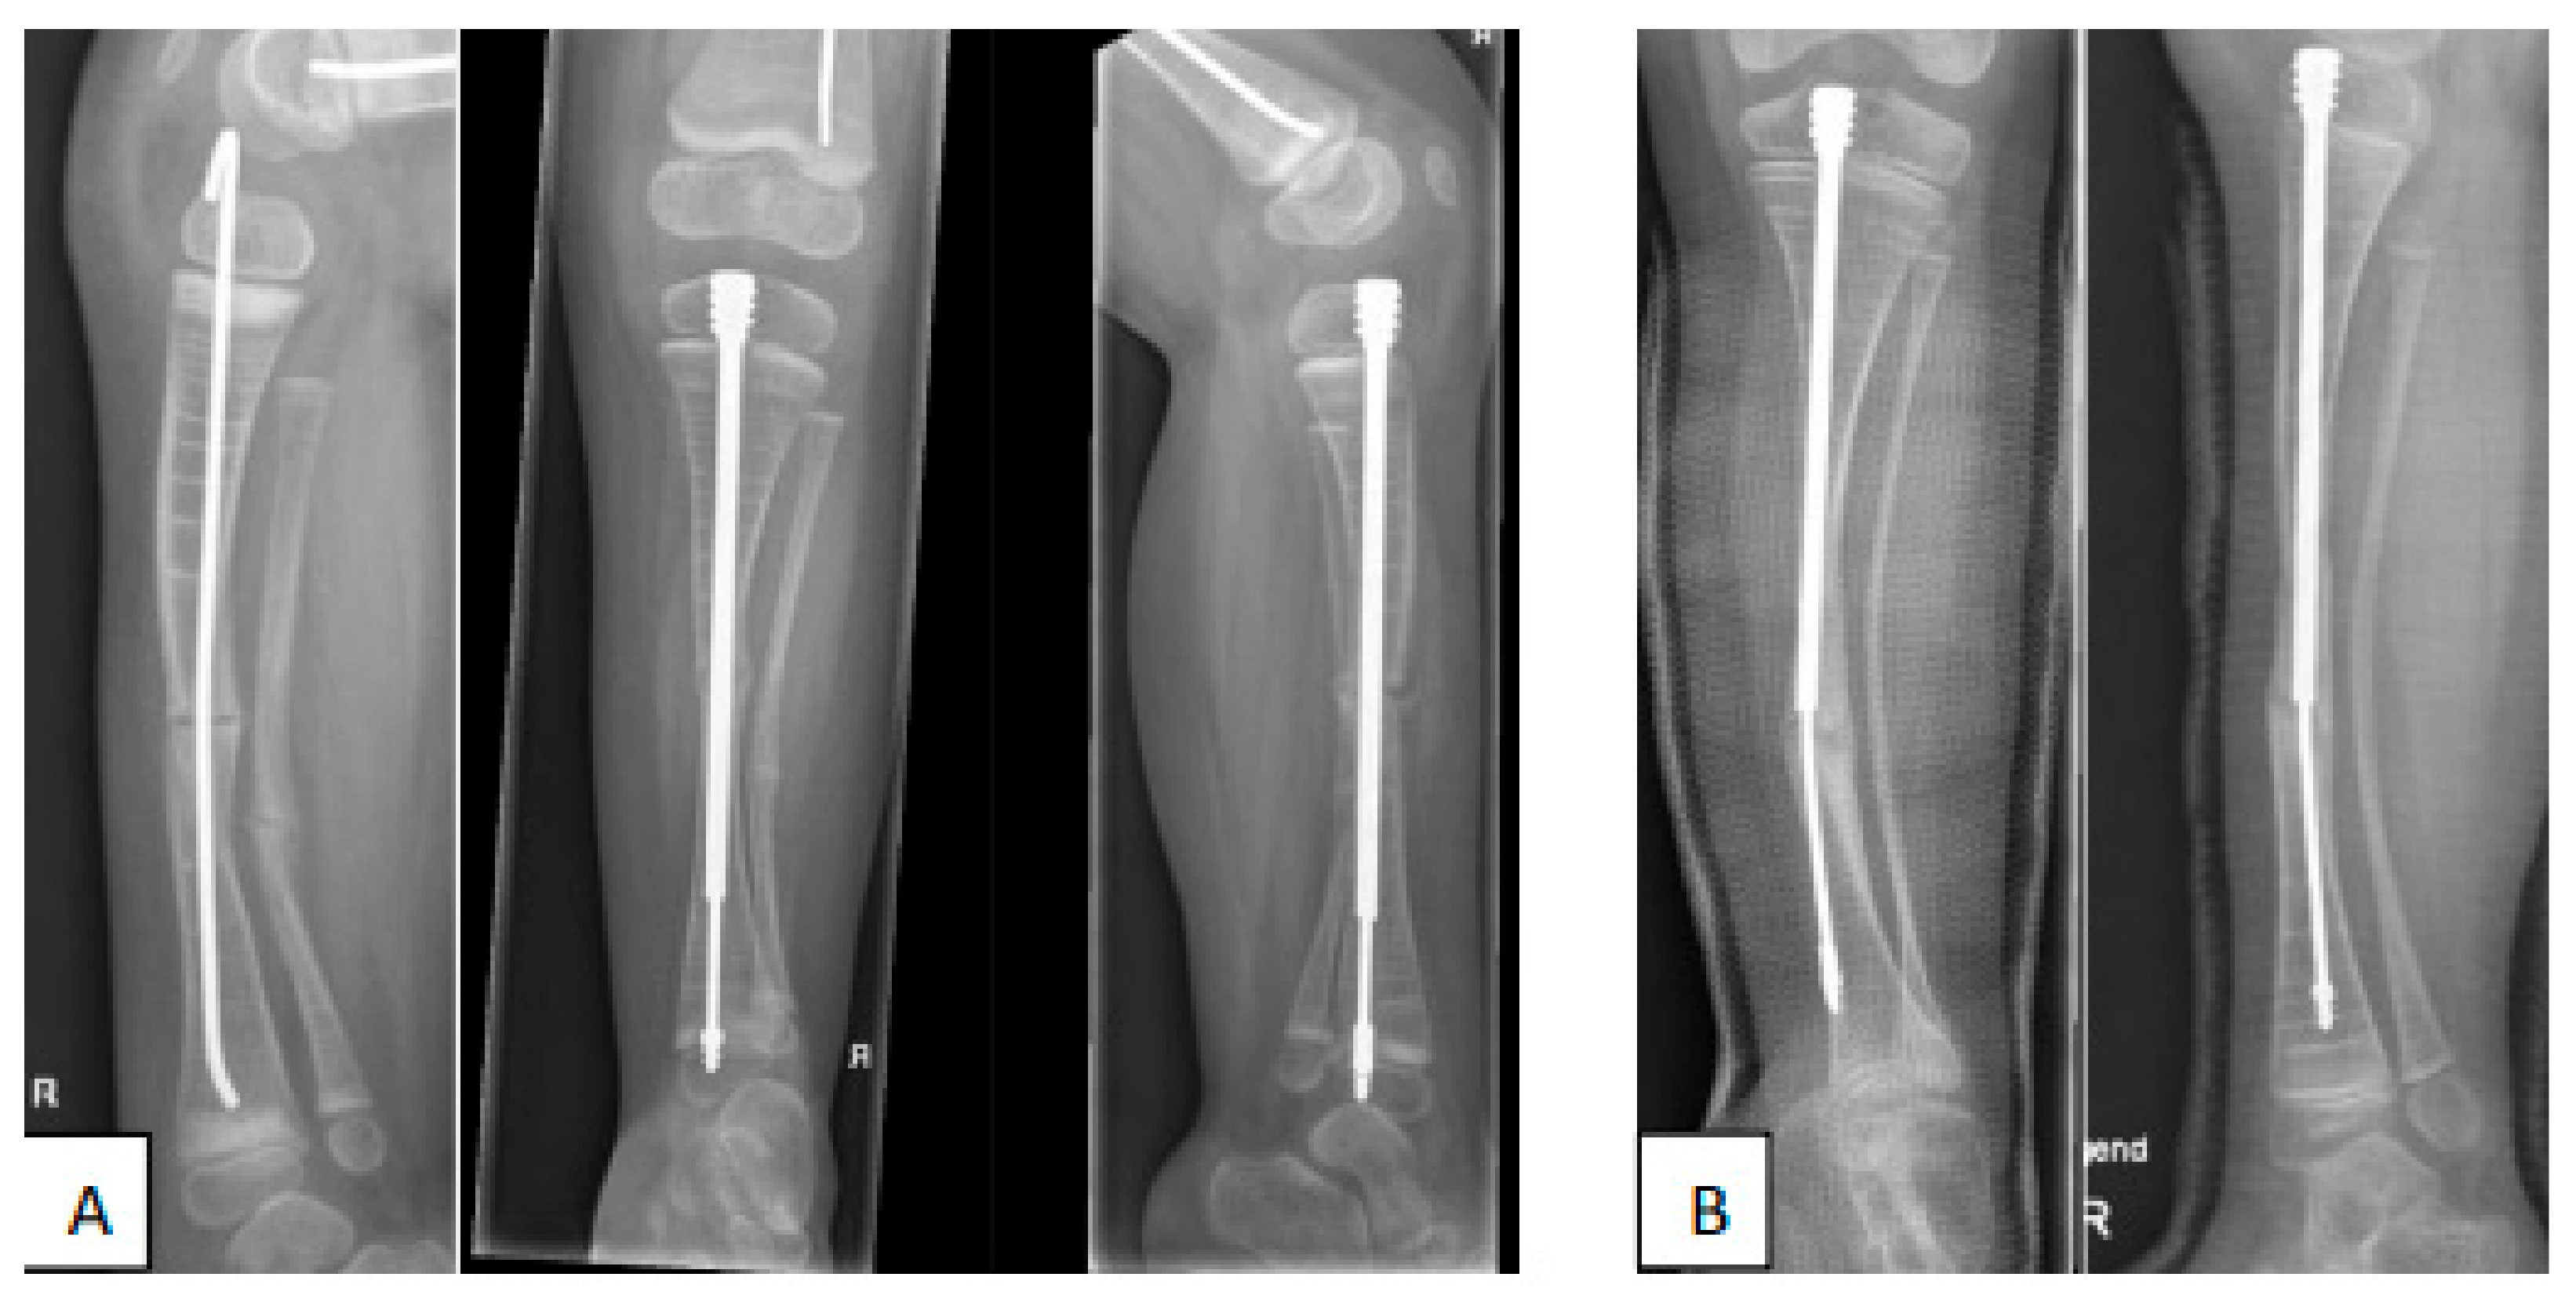

- Azzam, K.A.; Rush, E.T.; Burke, B.R.; Nabower, A.M.; Esposito, P.W. Mid-term Results of Femoral and Tibial Osteotomies and Fassier-Duval Nailing in Children With Osteogenesis Imperfecta. J. Pediatr. Orthop. 2018, 38, 331–336. [Google Scholar] [CrossRef]

- Sakkers, R.J.; Montpetit, K.; Tsimicalis, A.; Wirth, T.; Verhoef, M.; Hamdy, R.; Ouellet, J.A.; Castelein, R.M.; Damas, C.; Janus, G.J.; et al. A roadmap to surgery in osteogenesis imperfecta: Results of an international collaboration of patient organizations and interdisciplinary care teams. Acta Orthop. 2021, 92, 608–614. [Google Scholar] [CrossRef]